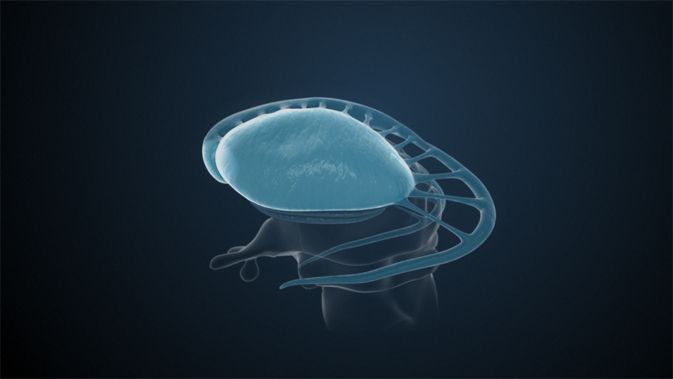

Insellappen

Der Insellappen ist ein eingesenkter Teil des Cortex (Großhirnrinde), der durch Frontal-, Temporal– und Parietallappen verdeckt wird. Diese Überlagerung wird Opercula (Deckel) genannt. Die Insula hat Einfluss auf die Motorik und Sensorik der Eingeweide und gilt in der Schmerzverarbeitung als Verbindung zwischen kognitiven und emotionalen Elementen.

Operculum

Rindengebiete von Frontal-, Schläfen– und Temporallappen an der seitlichen Innenfurche. Das Operculum bedeckt die Inselrinde.